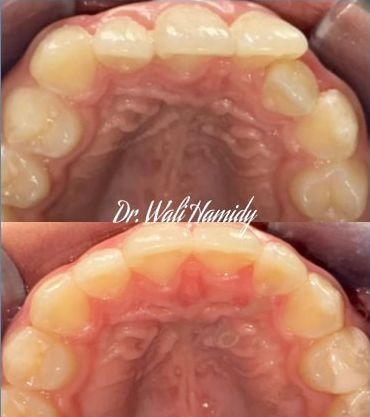

Check out our Invisalign® treatment gallery to see how this orthodontic service can straighten your teeth and improve your smile. Contact La Jolla Dental Image at 858-202-0481 today to make an appointment with our dentist, Dr. Wali Hamidy, and learn more about Invisalign clear aligners in La Jolla, California.